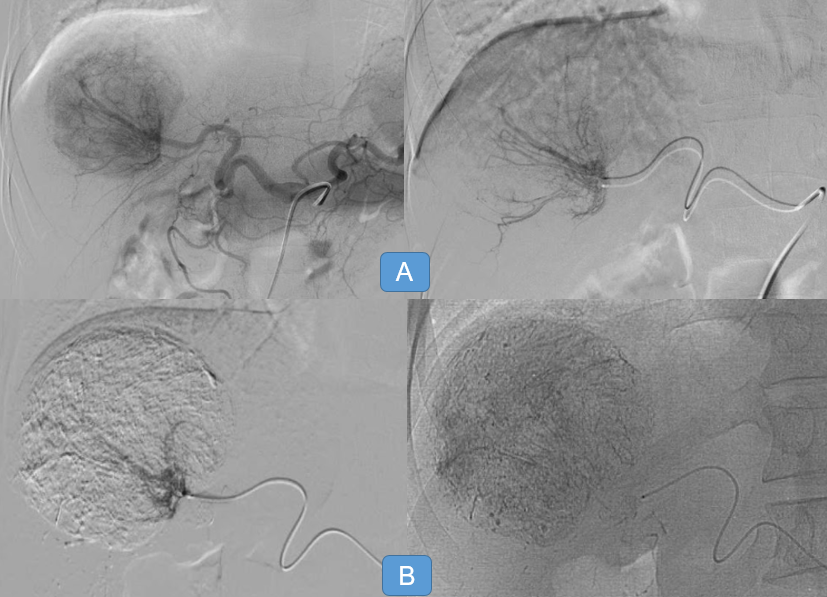

Hình 3: Chụp và can thiệp khối u gan bằng cồn tuyệt đối

– Chụp ĐM gan đánh giá ĐM nuôi u, tiếp cận siêu chọn lọc nhánh ĐM nuôi u bằng vi ống thông, chụp đánh giá.

– Chuẩn bị vật liệu nút mạch tức là cồn tuyệt đối pha cùng lipiodol tỉ lệ phụ thuộc từng ca bệnh

– Bơm hỗn dịch trên dưới sự hỗ trợ của máy DSA.